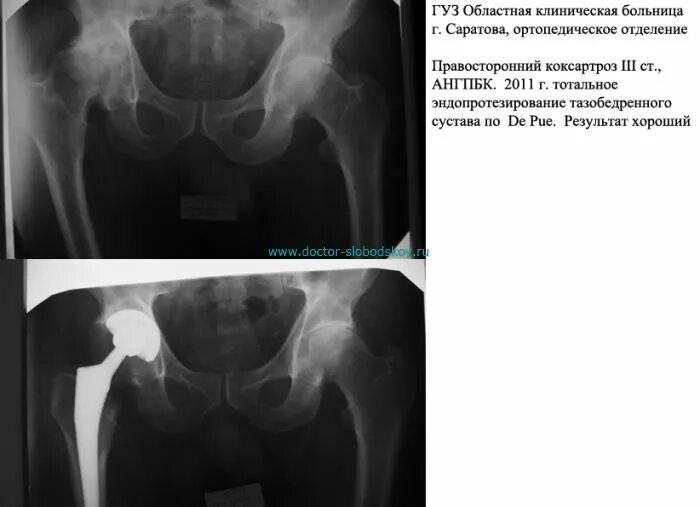

Коксартроз тазобедренного 1 стадии